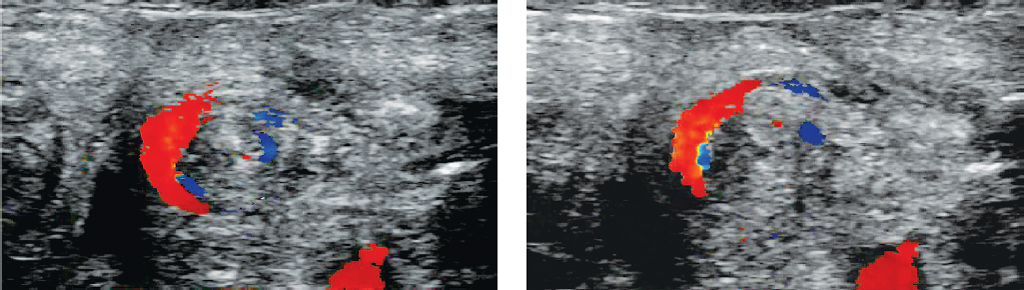

Главный ультразвуковой признак, демонстрирующий наличие заворота средней кишки, так называемый whirlpool sign, или симптом водоворота (рис. 5), представляющий собой оборот брыжейки и ВБВ вокруг ВБА, частично или полноценно наблюдался у трех из четырех пациентов, которым интраоперационно был поставлен синдром Ледда.

Рис. 5. Whirlpool sign, или симптом водоворота, выявленный у новорожденного, цветовое допплеровское сканирование

Fig. 5. Whirlpool sign, or whirlpool symptom, detected in a newborn, color Doppler imaging

Данное состояние в трех случаях ликвидировано одноименной операцией, в четвертом случае были рассечены брюшные тяжи, расправлены брыжейка тонкой кишки, фиксирована в правом фланке живота восходящая ободочная кишка. От расположения толстой кишки в левый фланк было принято воздержаться в связи с правильной фиксацией поперечно-ободочной кишки и связки Трейтца. В остальных случаях атипичное взаиморасположение сосудов состояло преимущественно в правостороннем расположении артерии относительно вены (рис. 6).